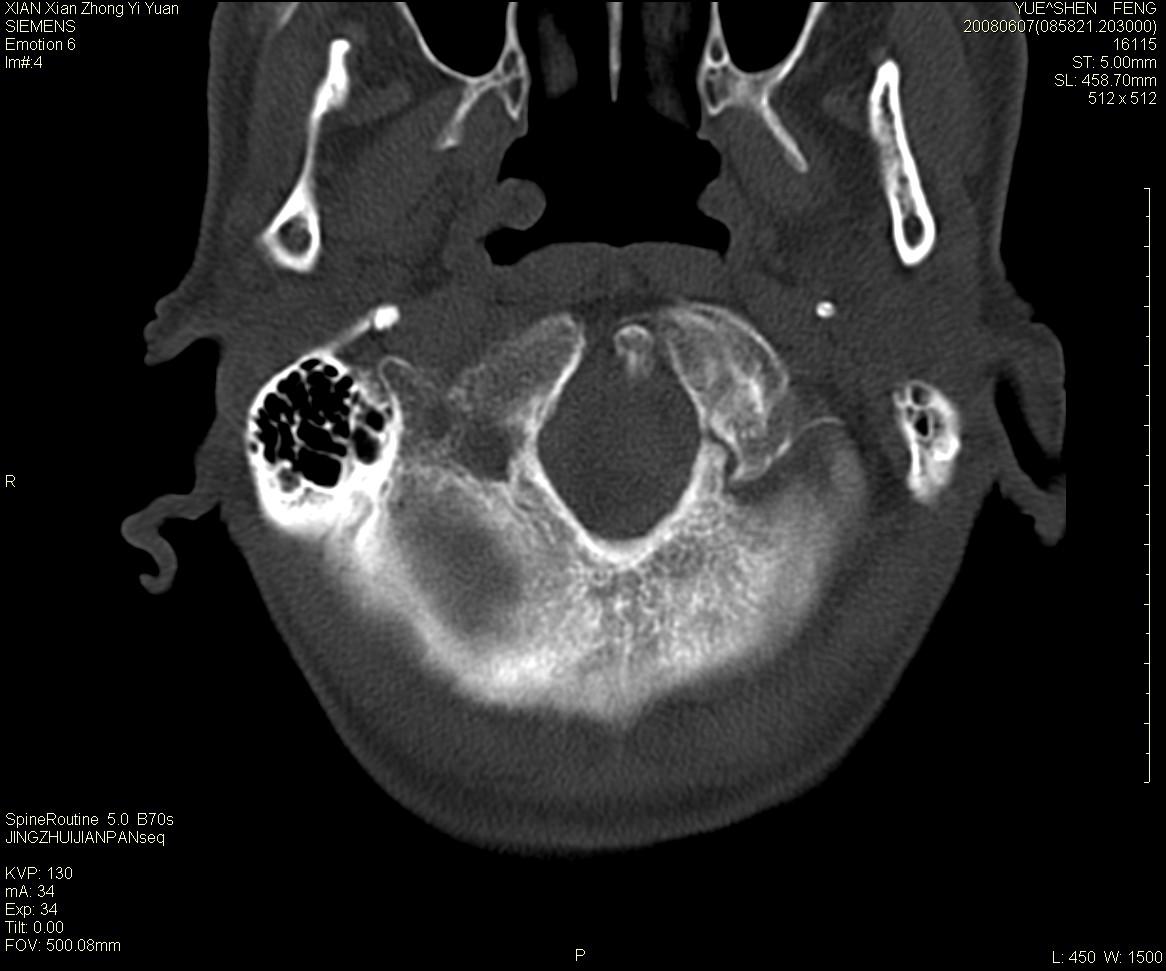

标题: CT13889:M72,颈部疼痛两年,近来加重。 [打印本页]

标题: CT13889:M72,颈部疼痛两年,近来加重。

作者: XIANXIANZHONGYI    时间: 2008-6-9 18:06

考虑浆细胞瘤

依据:

1 老年男性,颈部疼痛两年余。

2 ct:枢椎椎体显示膨胀性溶骨性骨质破坏,受损区域较大,边界清晰,其中似可见有小囊状结构,并残存有少量的骨小梁。病变与正常骨组织之间有一狭窄的分界区。受损部位部分边缘显示轻度骨质硬化。病灶突破骨皮质并在椎管形成软组织肿块影。

影像学检查:骨骼x线表现为单一部位的溶骨性改变,受损区域较大,边界清晰,其中可见有小囊状结构,少数可残存有少量的骨小梁。病变与正常骨组织之间有一狭窄的分界区。部分患者可见到病理性骨折,少数表现为受损部位的骨质硬化。ct和磁共振(mri)检查可以更加清晰地显示病损范围和性质以及周围软组织情况,并可能发现x线未显示的病灶以及更准确地判断骨髓是否受累。骨孤立性浆细胞瘤的ct和mri表现为扩张性溶骨性改变,骨质的破坏区完全被软组织肿块所代替,骨质膨胀,边界清晰,常突破骨皮质并在附近形成软组织肿块影。脊柱受累还可深入到锥管压迫神经束或神经根。